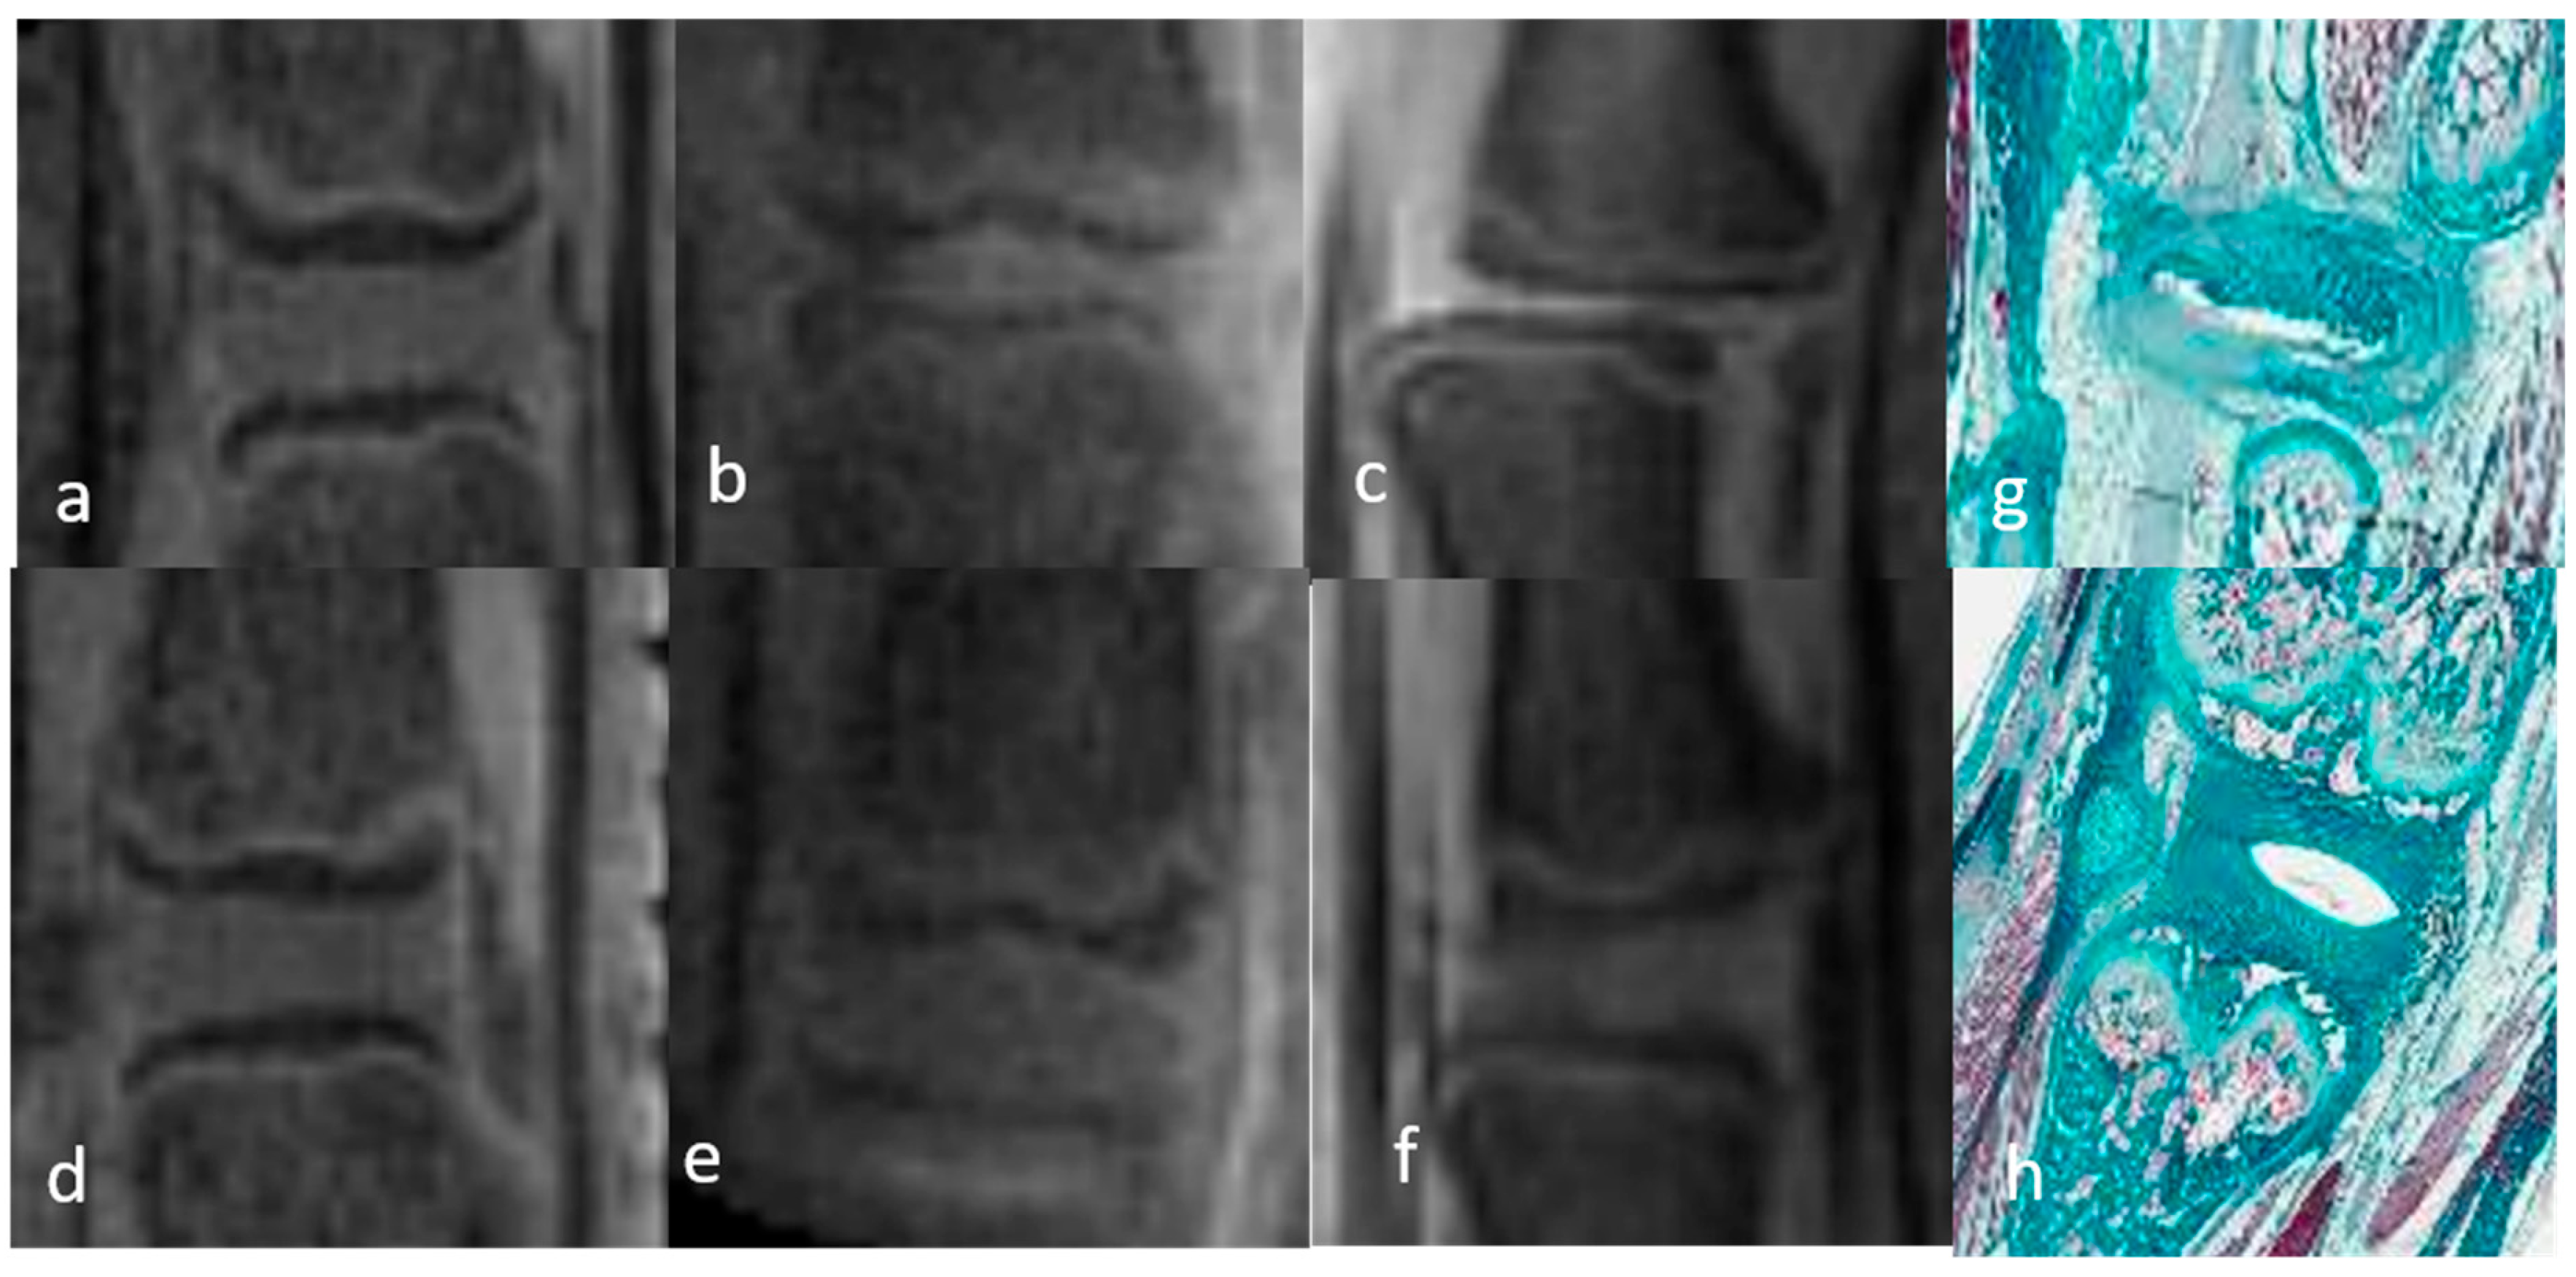

3.1.1. Qualitative Analysis of the Normal DVC (Table 1 and Table 2)

3.1.2. Qualitative Analysis of the DVC in DDD Rats (Table 3)

3.3. Histological Evaluation